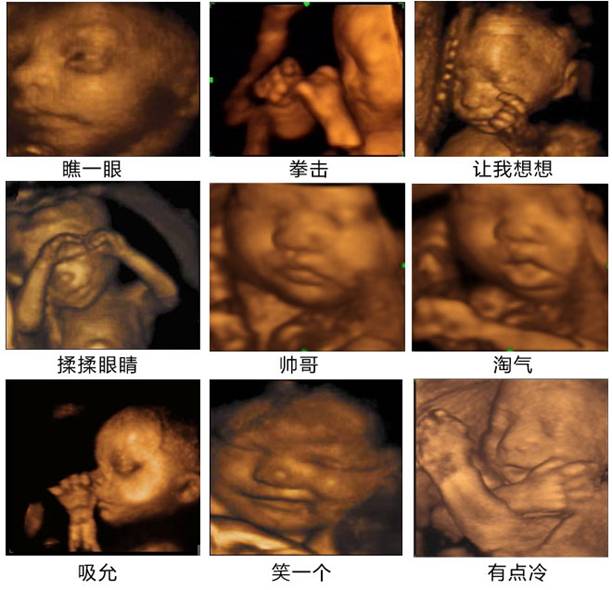

运用四维技术为胎儿进行健康检查

准妈妈的4D影院